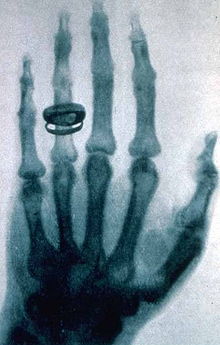

Сделанная В. К. Рентгеном фотография (рентгенограмма) руки Альберта фон Кёликера

Рентгеновское излучение было открыто Вильгельмом Конрадом Рёнтгеном. Он был первым, кто опубликовал статью о рентгеновских лучах, которые он назвал X-лучами (x-ray). Статья Рентгена под названием «О новом типе лучей» была опубликована 28-го декабря 1895 года в журнале Вюрцбургского физико-медицинского общества.

Применение: При помощи рентгеновских лучей можно «просветить» человеческое тело, в результате чего можно получить изображение костей, а в современных приборах и внутренних органов (см. также рентгенография и рентгеноскопия). При этом используется тот факт, что у содержащегося преимущественно в костях элемента кальция (Z=20) атомный номер гораздо больше, чем атомные номера элементов, из которых состоят мягкие ткани, а именно водорода (Z=1), углерода (Z=6), азота (Z=7), кислорода (Z=8). Кроме обычных приборов, которые дают двумерную проекцию исследуемого объекта, существуют компьютерные томографы, которые позволяют получать объёмное изображение внутренних органов.